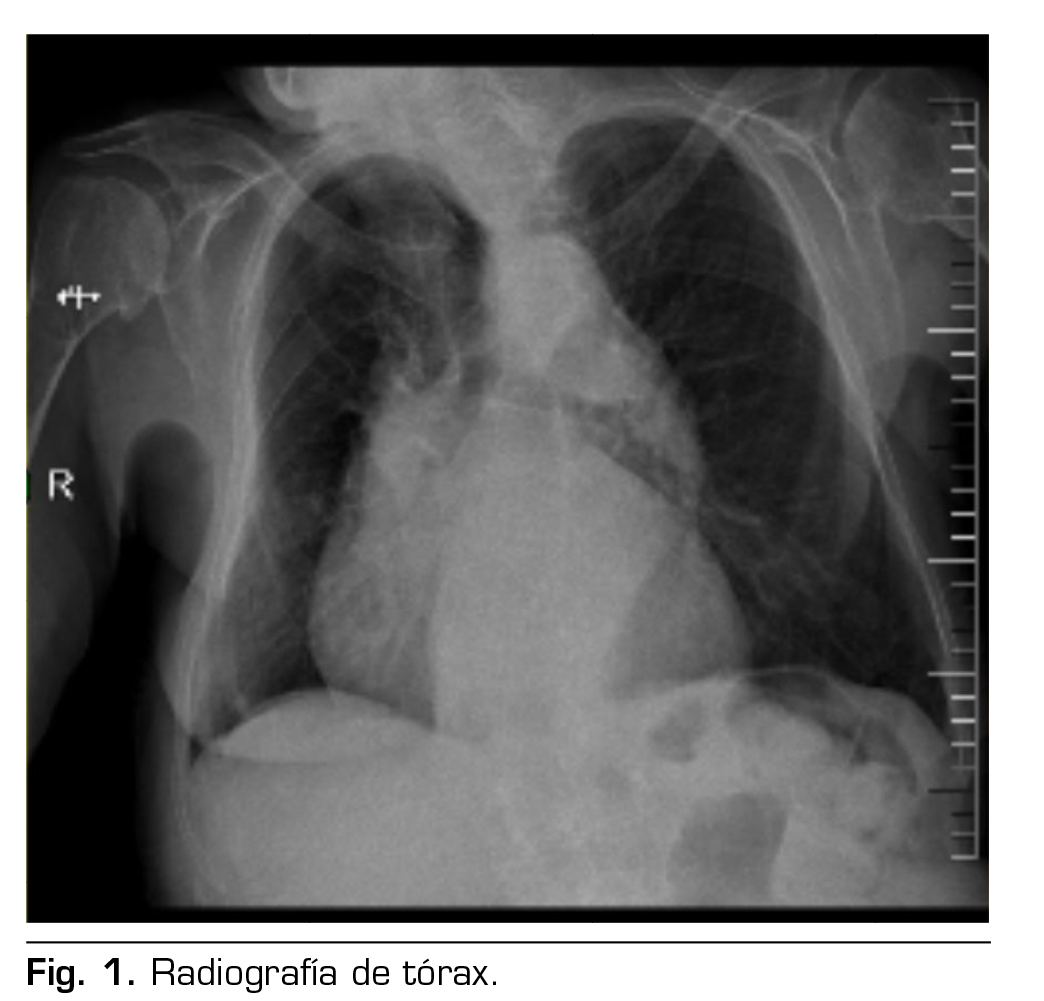

Presentamos el caso de una paciente de 88 años con diagnóstico de hernia inguinal izquierda que fue programada para hernioplastia electiva por cirugía ambulatoria en un hospital de día. En el estudio preanestésico se recoge que tiene antecedentes médicos de: hipertensión arterial controlada, fibrilación auricular en tratamiento con apixabán e insuficiencia cardiaca crónica compensada NYHA II, enfermedad pulmonar obstructiva con uso de oxígeno domiciliario nocturno, y no tiene antecedentes tromboembólicos; como antecedentes quirúrgicos: corrección de hernia discal a nivel de L5-S1 hace aproximadamente 20 años. Otros antecedentes de interés son los siguientes: cifoescoliosis moderada–severa, en imágenes diagnósticas como la radiografía de tórax anteroposterior, se observa cifoescoliosis severa y desplazamiento de mediastino a predominio derecho, como se muestra en la Figura 1; tiene un control ecocardiográfico que concluye función sistólica conservada, hipertrofia de ventrículo izquierdo, insuficiencia-estenosis aórtica severa, insuficiencia mitral moderada, insuficiencia tricuspídea severa, hipertensión pulmonar severa y dilatación moderada de aurícula izquierda. En el examen físico se confirma la cifoescoliosis dorsolumbar moderada-severa; en la evaluación de la vía aérea, se observa que tiene Mallampati 1, sin criterios de vía aérea difícil; analítica preoperatoria sin alteraciones de interés, paciente ASA III.